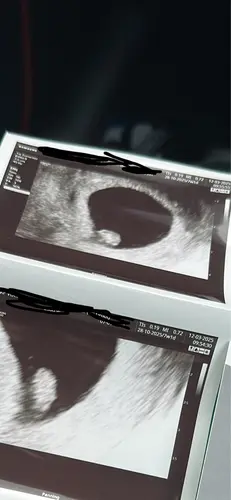

Tweeling! Zo spannend hoe het ontwikkeld de aankomende tijd. ♥️